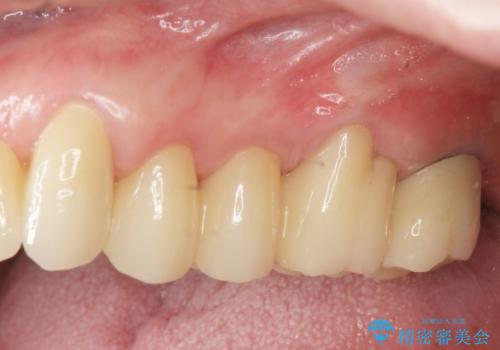

[ 重度歯周病 ] インプラント・義歯による咬合再構築

![[ 重度歯周病 ] インプラント・義歯による咬合再構築の症例 治療前](https://seimitsushinbi.jp/wp/wp-content/uploads/2021/07/0a652e75d5f31b51f66fbb3c46093249-500x350.jpg?v=1626759388)

![[ 重度歯周病 ] インプラント・義歯による咬合再構築の症例 治療後](https://seimitsushinbi.jp/wp/wp-content/uploads/2021/07/4c6838854beaf5801dbc7fde26492d6c-500x350.jpg?v=1626759531)